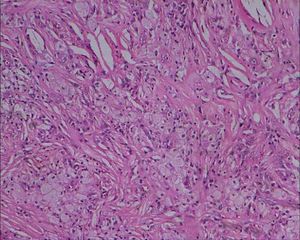

황색종은 피부 아래에 생기는 황색 콜레스테롤 덩어리 또는 그로 인해 발생하는 질환을 통칭한다. 다양한 유형이 있으며, 피부, 힘줄, 손바닥 등 신체 여러 부위에 나타날 수 있다. 황색종은 고지혈증, 당뇨병 등 다른 질환과 관련될 수 있으며, 액체 질소 요법, 고지혈증 치료, 외과적 절제 등의 방법으로 치료한다.

| 증상 | 피부 또는 힘줄에 콜레스테롤 침착 |

| 의학 분야 | 피부과학 |